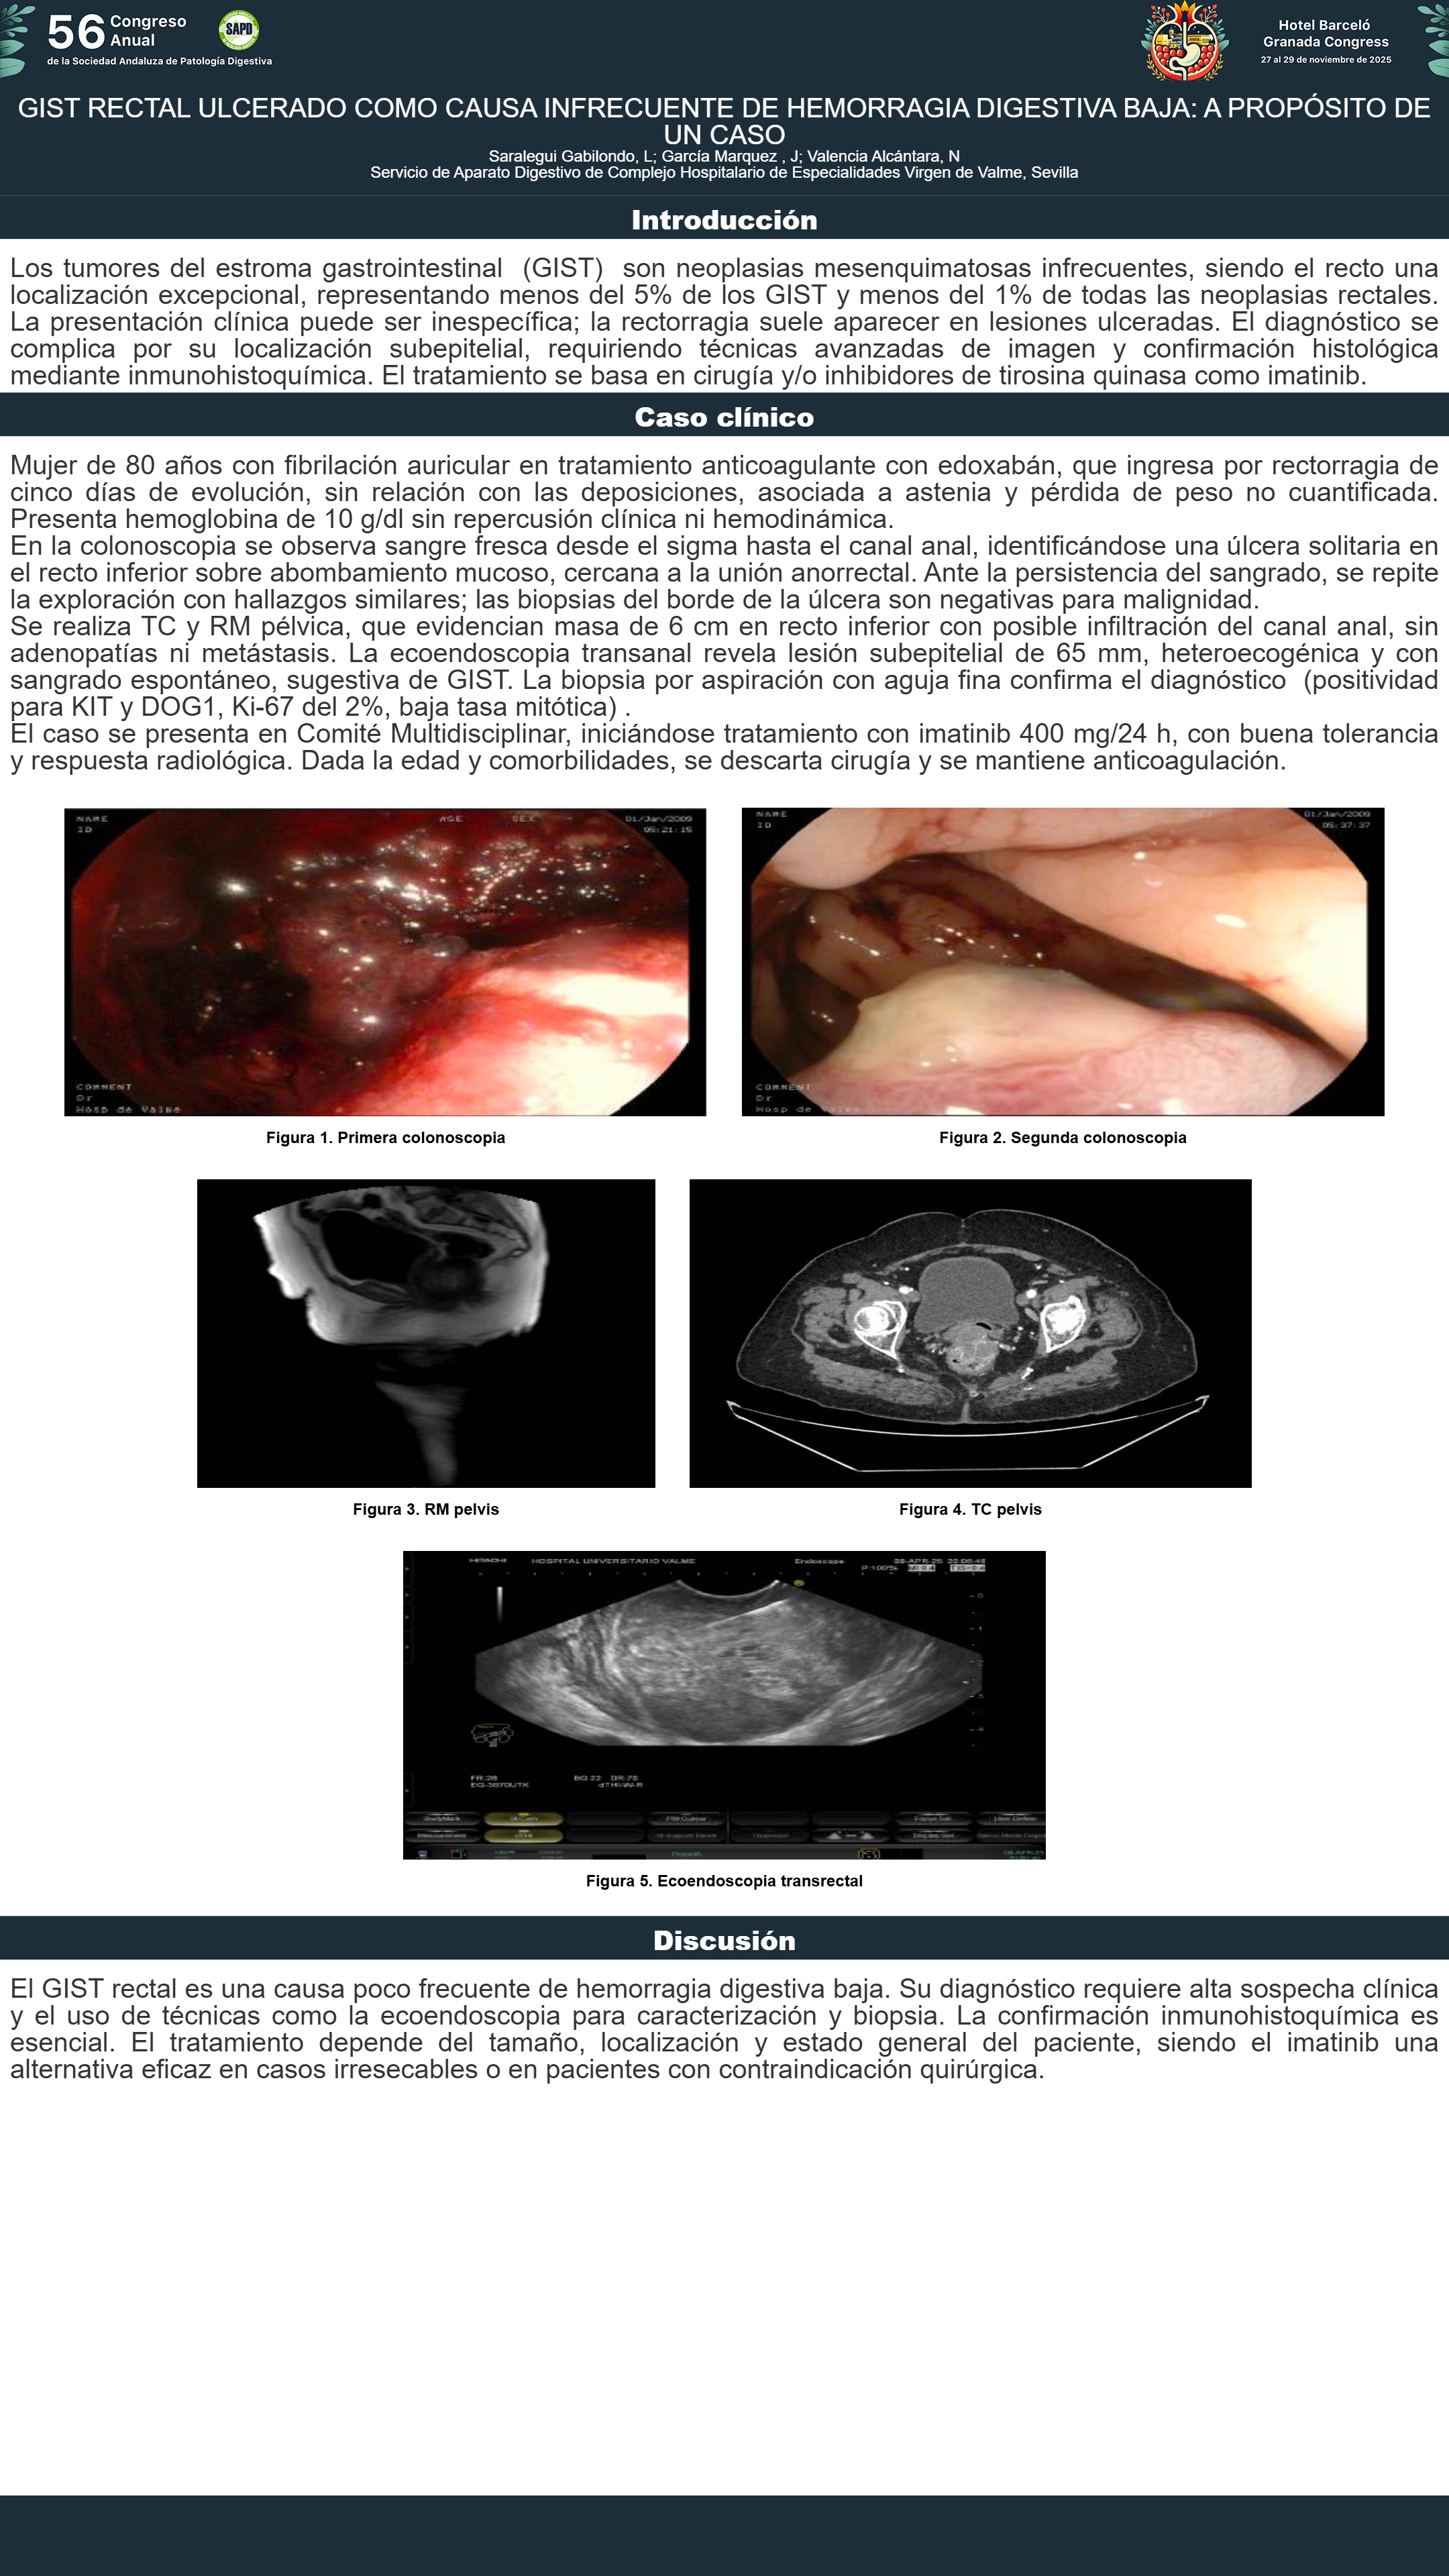

[CP-117] GIST RECTAL ULCERADO COMO CAUSA INFRECUENTE DE HEMORRAGIA DIGESTIVA BAJA: A PROPÓSITO DE UN CASO